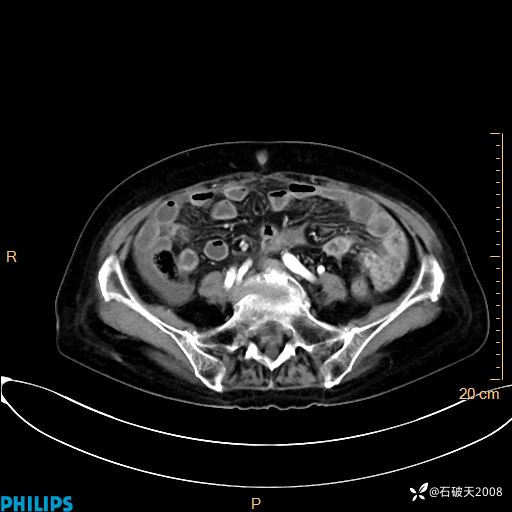

MIP